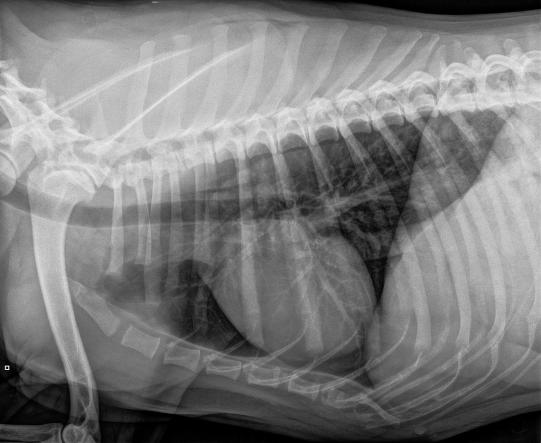

Im Auftrag der Hilfsorganisation waren Bruströntgen angefertigt worden - auf den Bildern sind keine offensichtliche Veränderungen am Herzen zu sehen, wie sie bei unbehandeltem Herzwurmbefall auftreten könnten. Der Laborbericht eines Schweizer Grosslabors (Labor A) zeigt aber, dass im Blut Dirofilaria-Antigen gefunden wurde - ein Hinweis auf einen Herzwurmbefall.